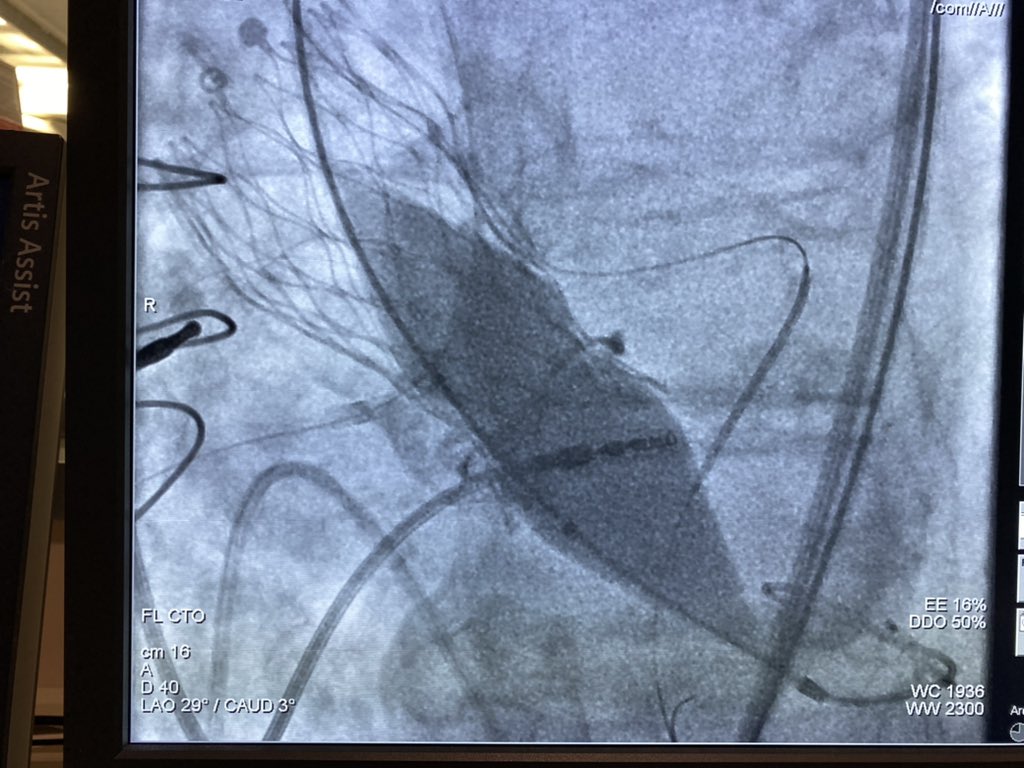

Combined bioprosthetic valve fracture (Crown n.19) and chimney stenting in valve-in-valve TAVR (Evolut R n.23). Final result.

Combined bioprosthetic valve fracture (Crown n.19) and chimney stenting in valve-in-valve TAVR (Evolut R n.23).